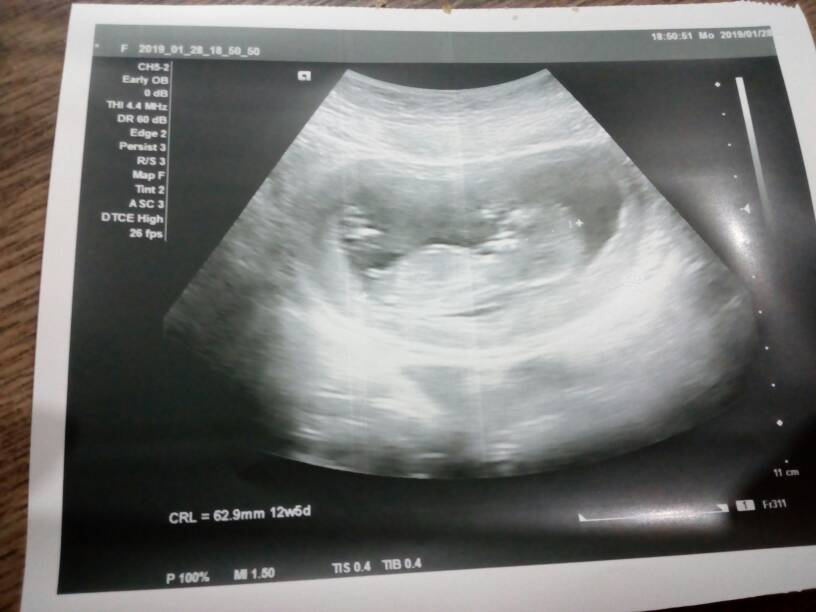

A ja byłam dzisiaj na wizycie i z maleństwem jest ok serduszko bije i już ma 6.3 cm tak rośniemy [emoji8]

IMG_20190128_192952.jpeg